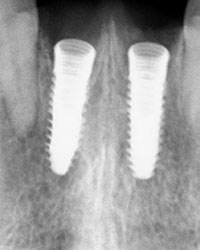

Decidimos: bajo anestesia local. previa asepsia y antisepsia, la limpieza de los alvéolos y la colocación de paralelos e implantes dentales.se colocan sus mismas coronas naturales para darle forma a los tejidos blandos y conservar papilas anatómicas.

Rx Panoramica Post Quirúrgica